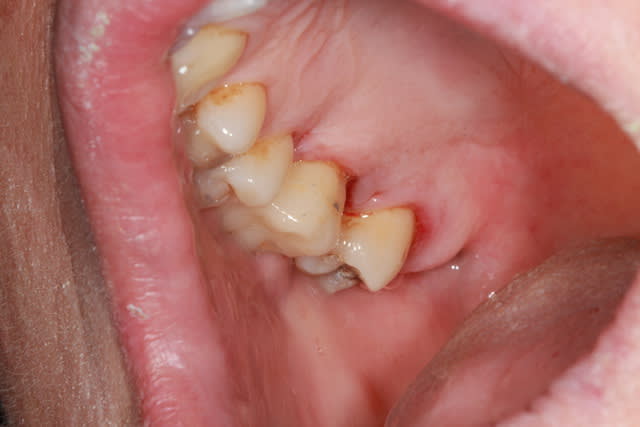

sur le cas que je vous ai montré plus haut , la limite est au moins 1mm supra gingival , dans l'émail.

j'ai préféré délabrer plus car contexte bruxomane et perte d'une paroi proximale

un cas réalisé depuis : une endocouronne réalisée la semaine dernière sur une nécrose d'origine paro ,

surfaçage + laser pendant la cuisson , a voir dans le temps...